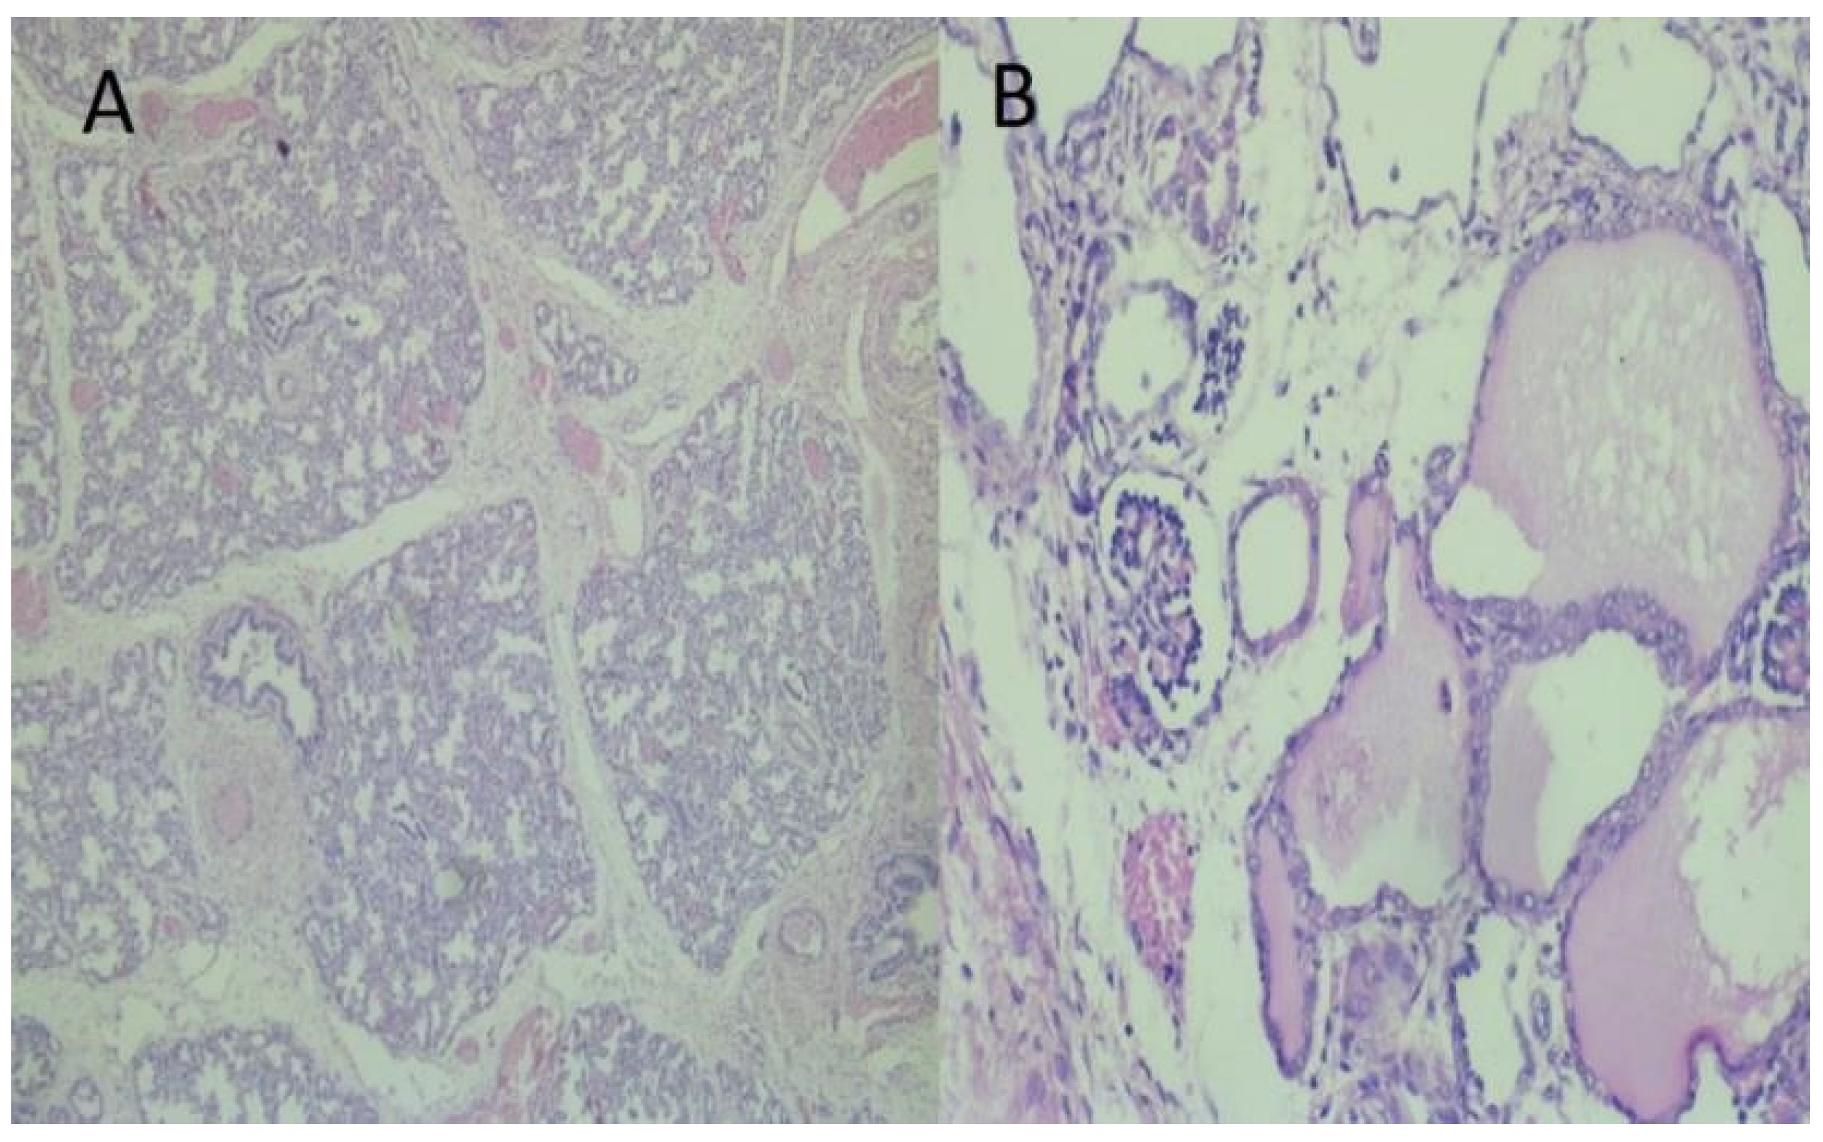

| Physical or autopsy findings | Mild nasal and ear compression | Bilateral ureteropelvic obstruction, dysplasia kidneys, severe PH | Bilateral renal dysplasia, Potter’s facies, severe PH | Urethral agenesis, severe PH | Autopsy refused | PH, PS facies, talipes equinovarus, polycystic kidneys |

| Microscopic findings | Not reported | Not reported | Not reported | Not reported | Reported | |